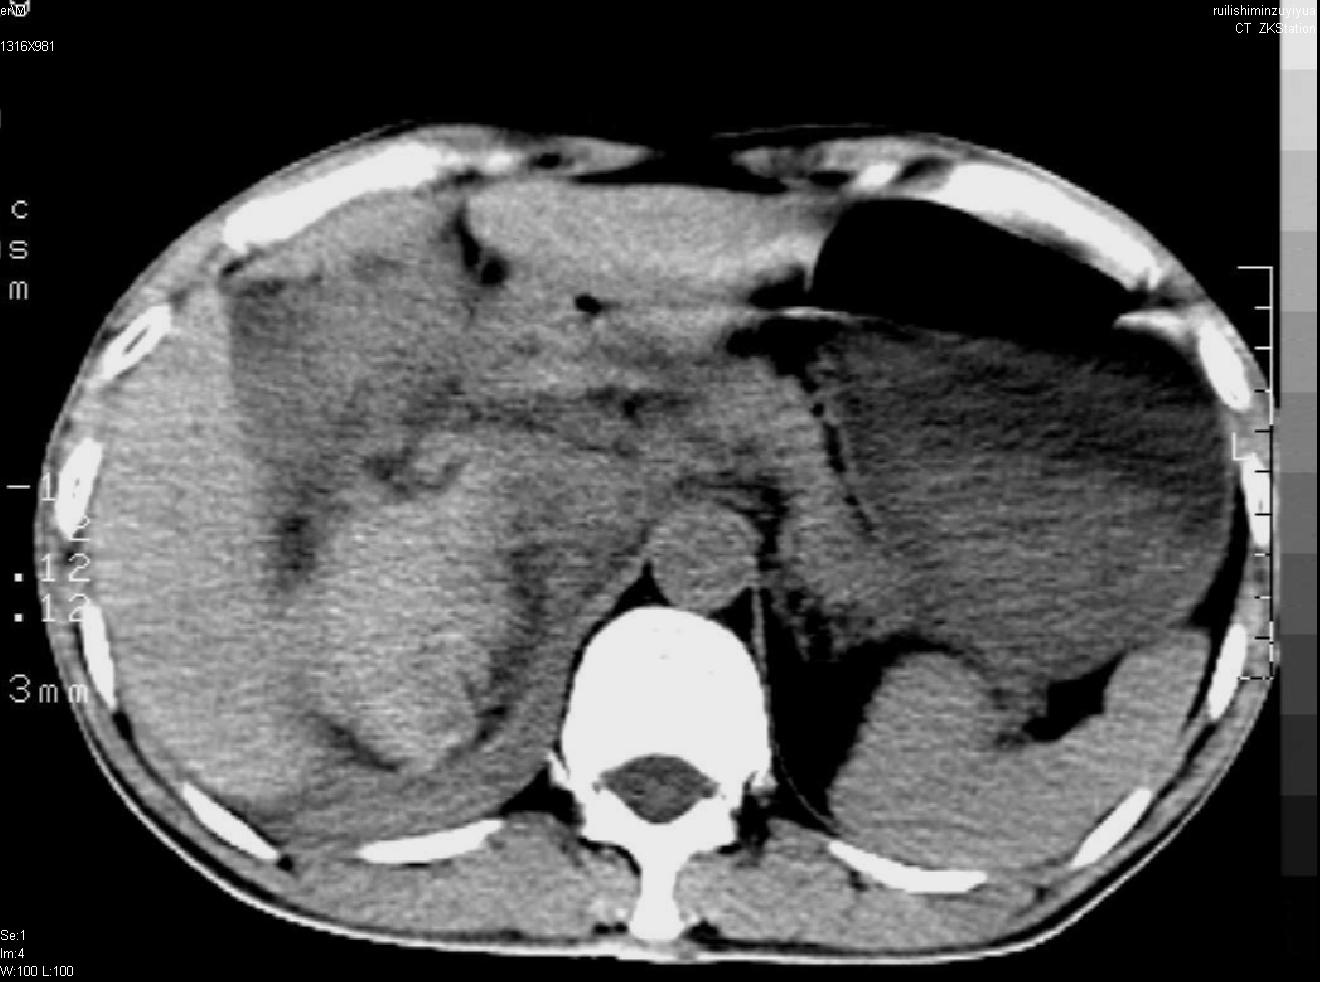

以下是引用liuyue在2007-12-3 6:27:00的发言:[br]右肾区可见密度不均匀、边缘欠清之肿块影,肾脏筋膜增厚,周围脂肪密度增高。右侧胸膜腔内可见少量液体密度影。考虑:1.右肾错构瘤(肾血管平滑肌脂肪瘤)可能性大。2.右侧少量胸腔积液。[br] 鉴别:1.肾脂肪肉瘤。2.肾平滑肌肉瘤。3.肾错构瘤恶变。